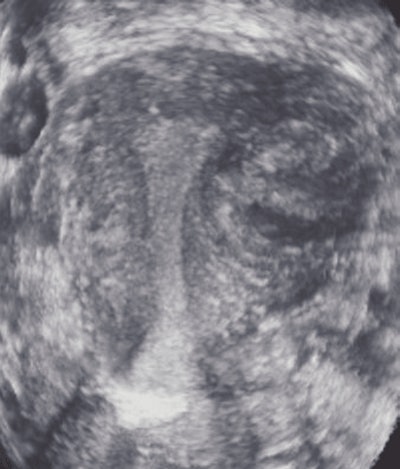

![]() |

For patients with an endometrium width of 5 mm or more, the 3D coronal view delivered either new data or data that confirmed a suspected diagnosis in 39% (11) of the 28 cases, compared to only four (12.5%) of 32 patients with an endometrium width less than 5 mm.

Thirty-four patients had fibroids that had been found with 2D ultrasound. In 24% (8) of these patients, the fibroids were seen more clearly with the 3D coronal view.

| A 40-year-old woman with a fibroid. Above, transverse view of uterus shows fibroid (calipers). Exact location of fibroid with respect to uterine cavity is unclear because posterior aspect of fibroid obscures side of endometrium. Below, coronal view shows that fibroid is not submucous, but is intramural without distorting shape of uterine cavity. Plane shown here was deemed by radiologist to be best plane to show closest relationship between fibroid and endometrium, showing that the fibroid did not extend into cavity but just abuts it. Benacerraf B, Shipp T, Bromely B, "Which Patients Benefit from a 3D Reconstructed Coronal View of the Uterus Added to Standard Routine 2D Pelvic Sonography?" (AJR 2008; 190:626-629). |